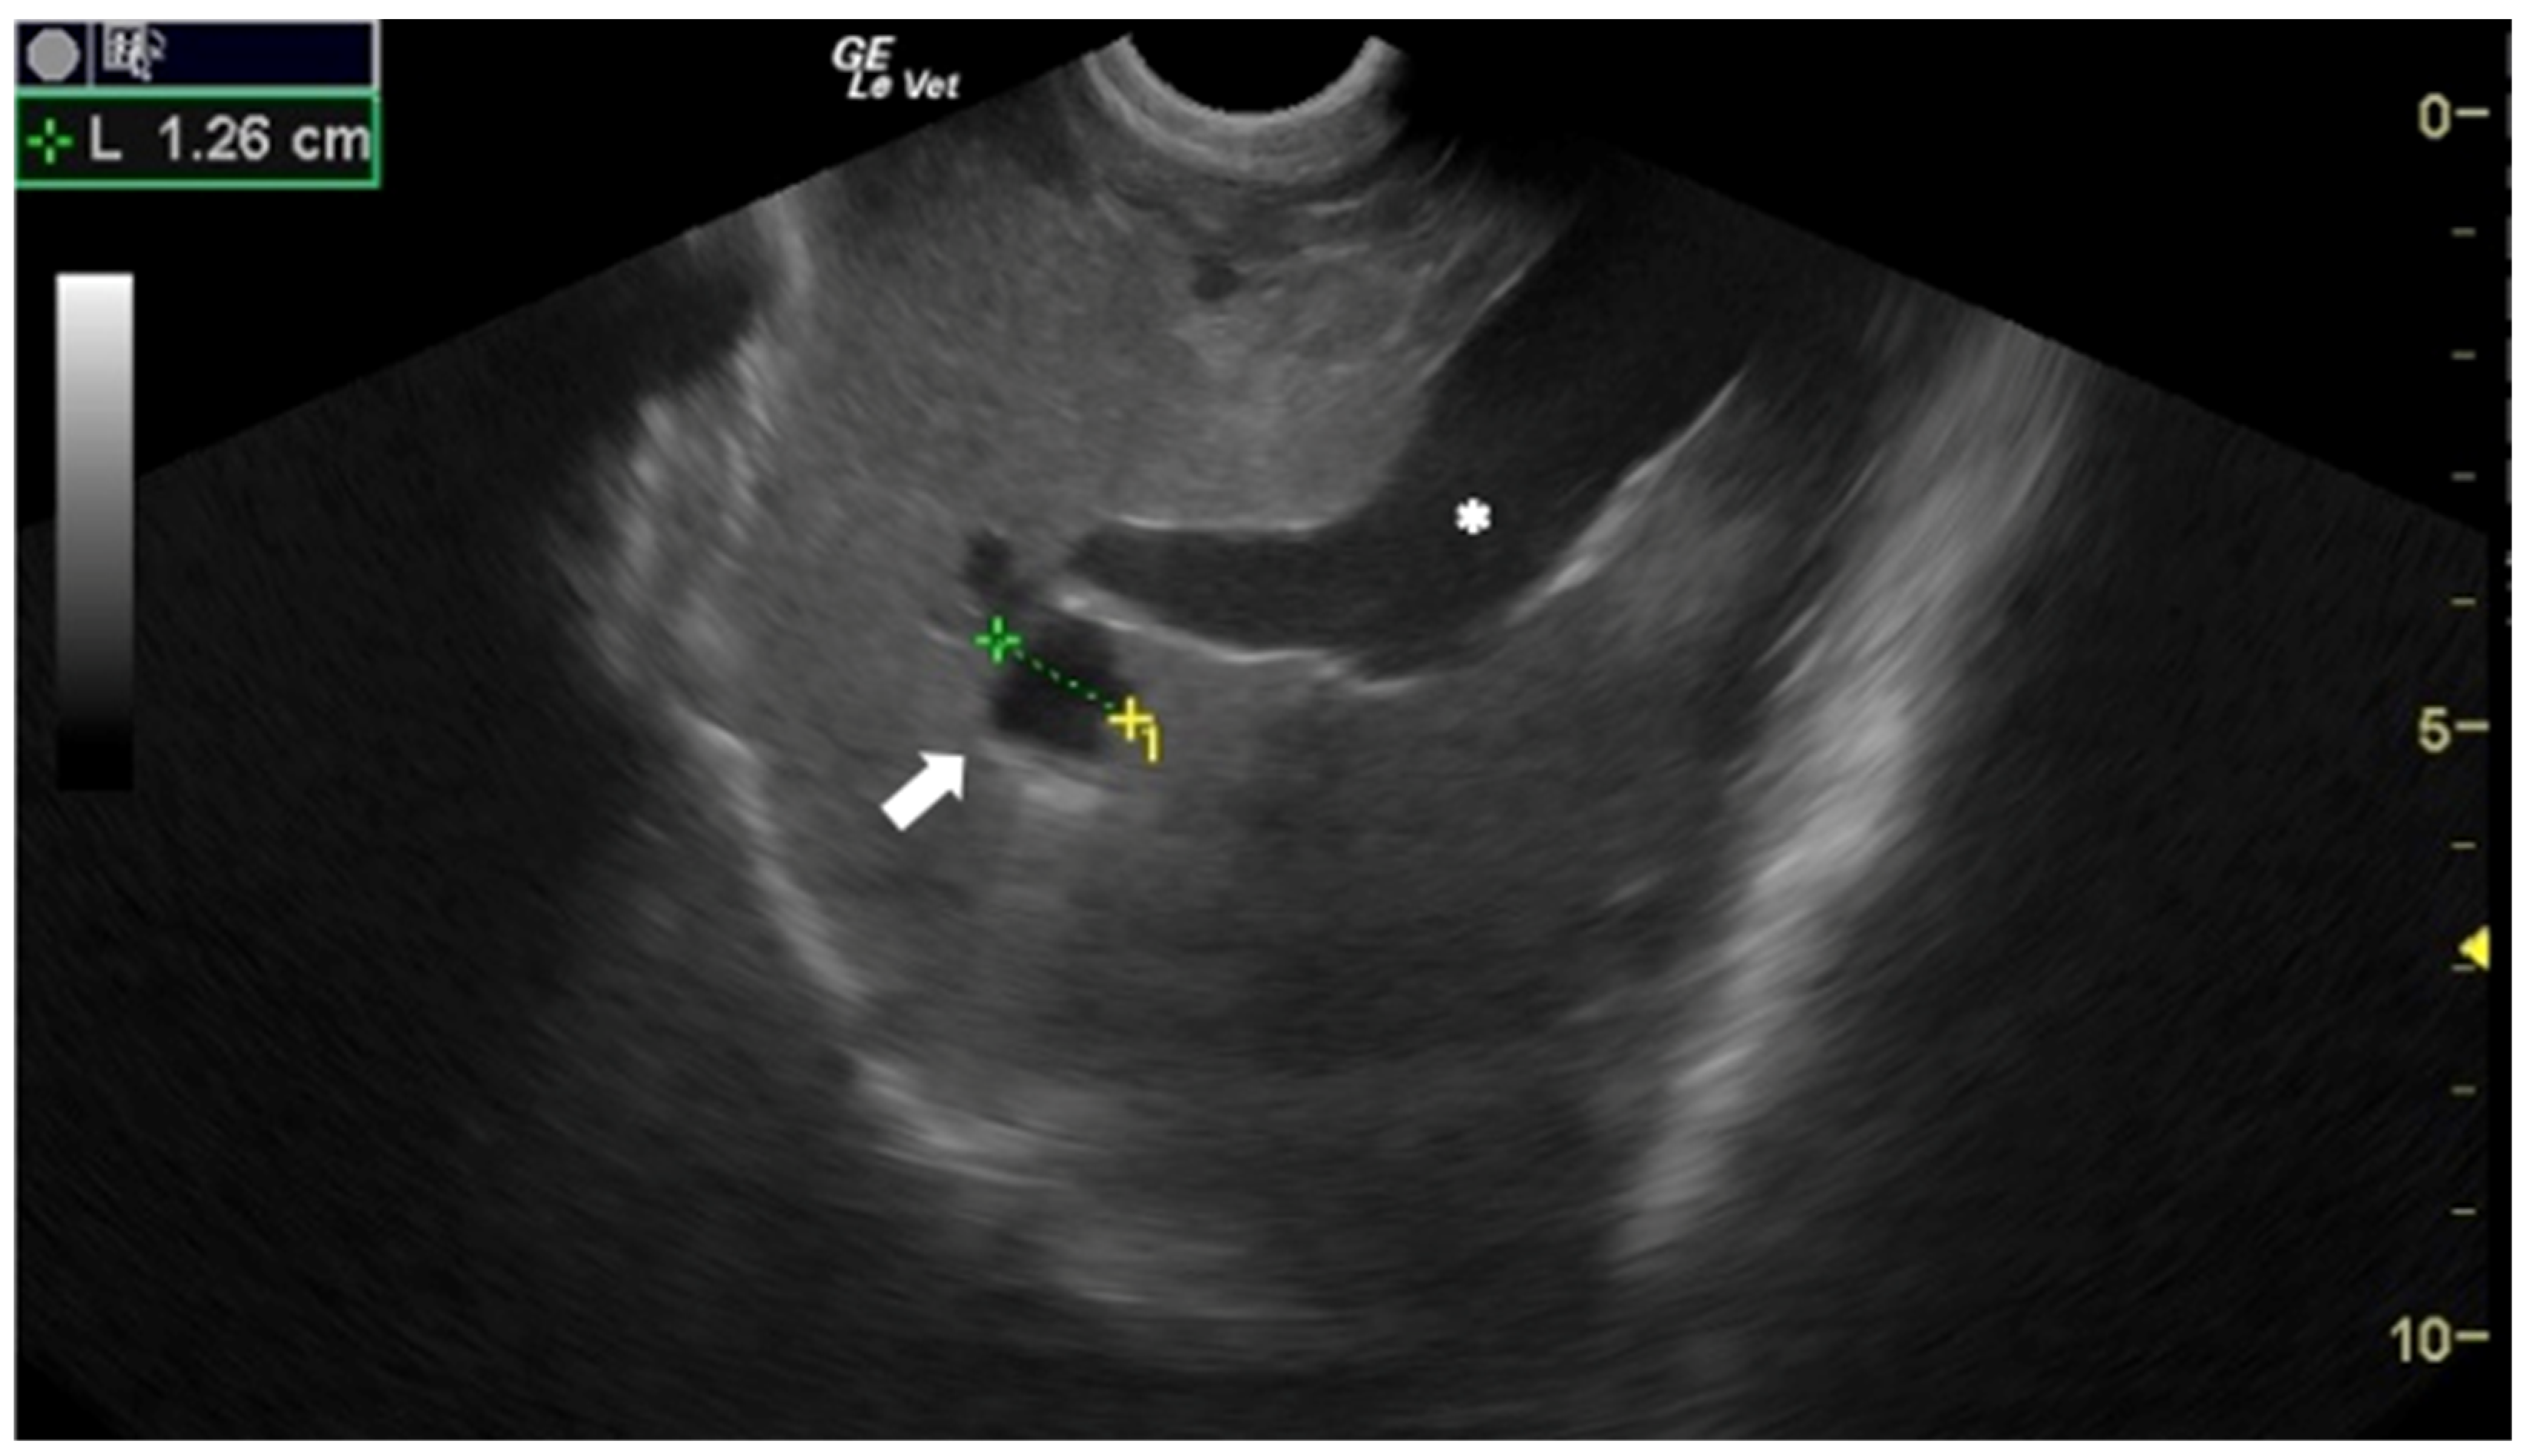

- Corda, A.; Dessì, G.; Varcasia, A.; Carta, S.; Tamponi, C.; Sedda, G.; Scala, M.; Marchi, B.; Salis, F.; Scala, A.; et al. Acute visceral cysticercosis caused by Taenia hydatigena in lambs: Ultrasonographic findings. Parasites Vectors 2020, 13, 568. [Google Scholar] [CrossRef]